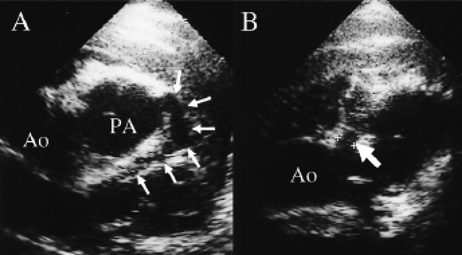

劇症型心筋炎では患者周囲に多くの輸液ルート,人工呼吸器,補助循環関連機器やモニターが存在するため,心エコーはベッドサイドでの非侵襲的検査として簡便かつ有用性の高い検査である.補助循環療法からの離脱評価のためにも必須の検査である.左室収縮能の低下,左室壁運動異常,左室腔の拡大,左室心筋壁の肥厚,房室弁逆流および心膜液貯留に着目することが必要である.一過性左室壁肥厚が心筋生検による病理所見とマッチしていたとの報告27)がある.左室腔の拡大と僧帽弁逆流が著明であるが他部位の弁逆流を認めない際は,拡張型心筋症との鑑別が必要で臨床所見との対比が重要である.また,乳児例では先天性冠動脈奇形との鑑別が重要となり冠動脈走行の確認が必須である.同奇形群は頻度としては稀であるが,左冠動脈肺動脈起始症28)や左冠動脈入口部閉鎖などを念頭におく必要がある.左冠動脈肺動脈起始症の冠動脈エコー所見をFig. 3に示す.両奇形では冠動脈入口部が一見正常開口にみえても,同部位の血流は逆行性である.正常冠動脈であることを証明するためには,冠動脈入口部の解剖学的開口の確認だけでなく同部位に順行性血流が存在するかを含めた観察を入念に行うべきである.

Pediatric Cardiology and Cardiac Surgery 32(5): 365-378 (2016)

Fig. 3 A case of anomalous left coronary artery from the pulmonary artery (4-month-old girl)

A: Echocardiography visualizes abnormal connection between the left anterior descending coronary artery and the main pulmonary artery (PA). B: The large right coronary artery originates from the aortic aorta without any abnormal blood vessels running. Ao: Aortic aorta, PA: Pulmonary artery. Cited from reference 28).